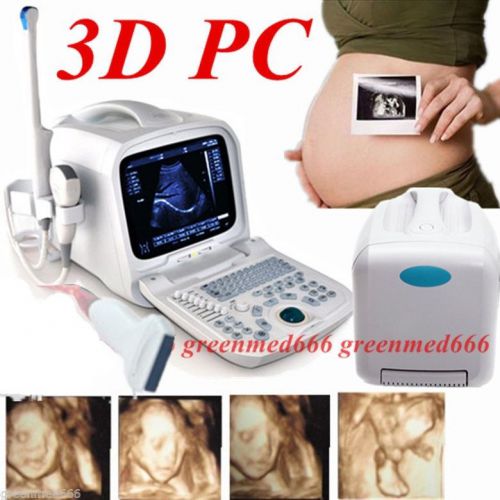

3D PC platform Full Digital Portable Ultrasound Scanner + Transvaginal Probe FDA

3D PC Platform Full Digital Portable Ultrasound Scanner Machine +Convex Probe CE

3D PC platform Full Digital Portable Ultrasound Scanner +Transrectal Probe Human

3D PC platform Ultrasound Scanner +3.5MHz Convex &Transvaginal Probe Internet

3D PC platform Ultrasound Scanner +7.5MHz Linear &Transvaginal 2 Probes Internet